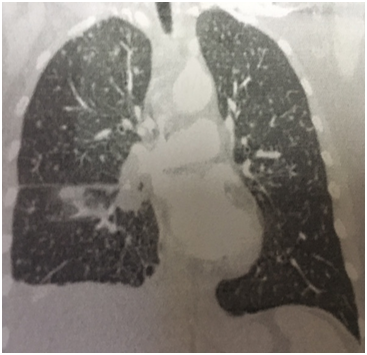

A 57 year old Caucasian female was admitted for dry cough, fever, loss of appetite and chest pain for three weeks. She had a history of tonsillectomy, ankylozing spondylitis, uveitis, pelvis fracture and tibia fracture. Her father died of colonic carcinoma. Her mother had hypertension and previous pulmonary tuberculosis. The patient was under treatment with certolizumab, methotrexate, and prednisolonefor ankylozing spondylitis and uveitis. Daily 300mg isoniazid was also given simultaneously with certolizumab for prophylaxis. Initial laboratory findings revealed WBC 8.2X103/mm3, hemoglobin 10.8g/dl, platelets 341X103mm3, lymphocytes 1.4X103/mm3, creatinine 0.74mg/dl, AST 18IU/L, ALT 18IU/Lmm3, LDH 167IU/L, albumine 3.56gr/dl, CRP 18.6 mg/dl, and calcium 9.1 mg/dl. ECG showed sinus ryhtm. Tuberculin test was negative. Chest x-rayshowed diffuse miliary nodules, alveolar infiltration in the right lower lobe, and right pleural effusion (Figure 1). Pleural protein 4.57g/dl, LDH 353U/L, and albumin 3.56g/dl. Pleural fluid had 1540cells/mm3 with a 74% lymphocyte ratio. Pleural fluid ADA was 114U/L (normal 0-40 U/L). The pleural fluid was exudative compatible with tuberculosis. Computed tomography of the thorax revealed diffuse miliary nodules, infiltration in the right anterior segment of the lower lobe, and right pleural effusion (Figures 2-4). Sputum stains was positive for acid-fast bacilli. Mycobacterium tuberculosis was isolated from the sputum culture. The final diagnosis was miliary tuberculosis associated with certolizumab occuring on the third month of treatment. The patient was commenced on pyrazinamide, isoniazid, rifampicine, and ethambutol treatment for tuberculosis while certolizumab treatment was stopped.

Figure 2 Coronal computed tomography revealing right lower anterior segmentinfiltration, right pleural effusion, and diffuse miliary nodules.

The patient had a negative tuberculin test and a normal chest x-ray before certolizumabtreatment. She was commenced on prophylactic isoniazid treatment because the patient had an exposure to active tuberculosis. Miliary tuberculosis with pleural effusion and right lower lobe infiltration occured on the third month of treatment. The patient had an appropriate screening for tuberculosis including medical history, tuberculine test, and chest x-ray before anti-TNF-α treatment was started. The sensitivity of the tuberculine test may have been restricted or diminished by the previous immunosuppressive treatment in our patient. The normal chest x-ray before treatment had also a low diagnostic yield for revealing sequela of past or current infection. Following treatment the right lower anterior segment infiltration was only identified at the computed tomography coronal image and was not detected in chest x-ray.